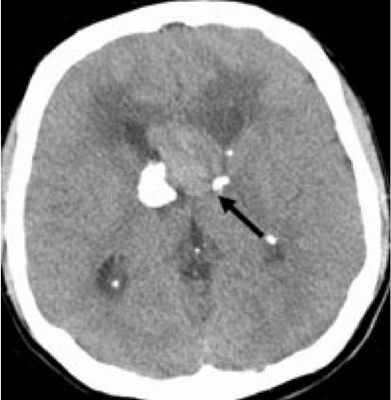

Субэпендимарные кальцификаты и корковые туберсы на КТ головного мозга ребенка с туберозным склерозом